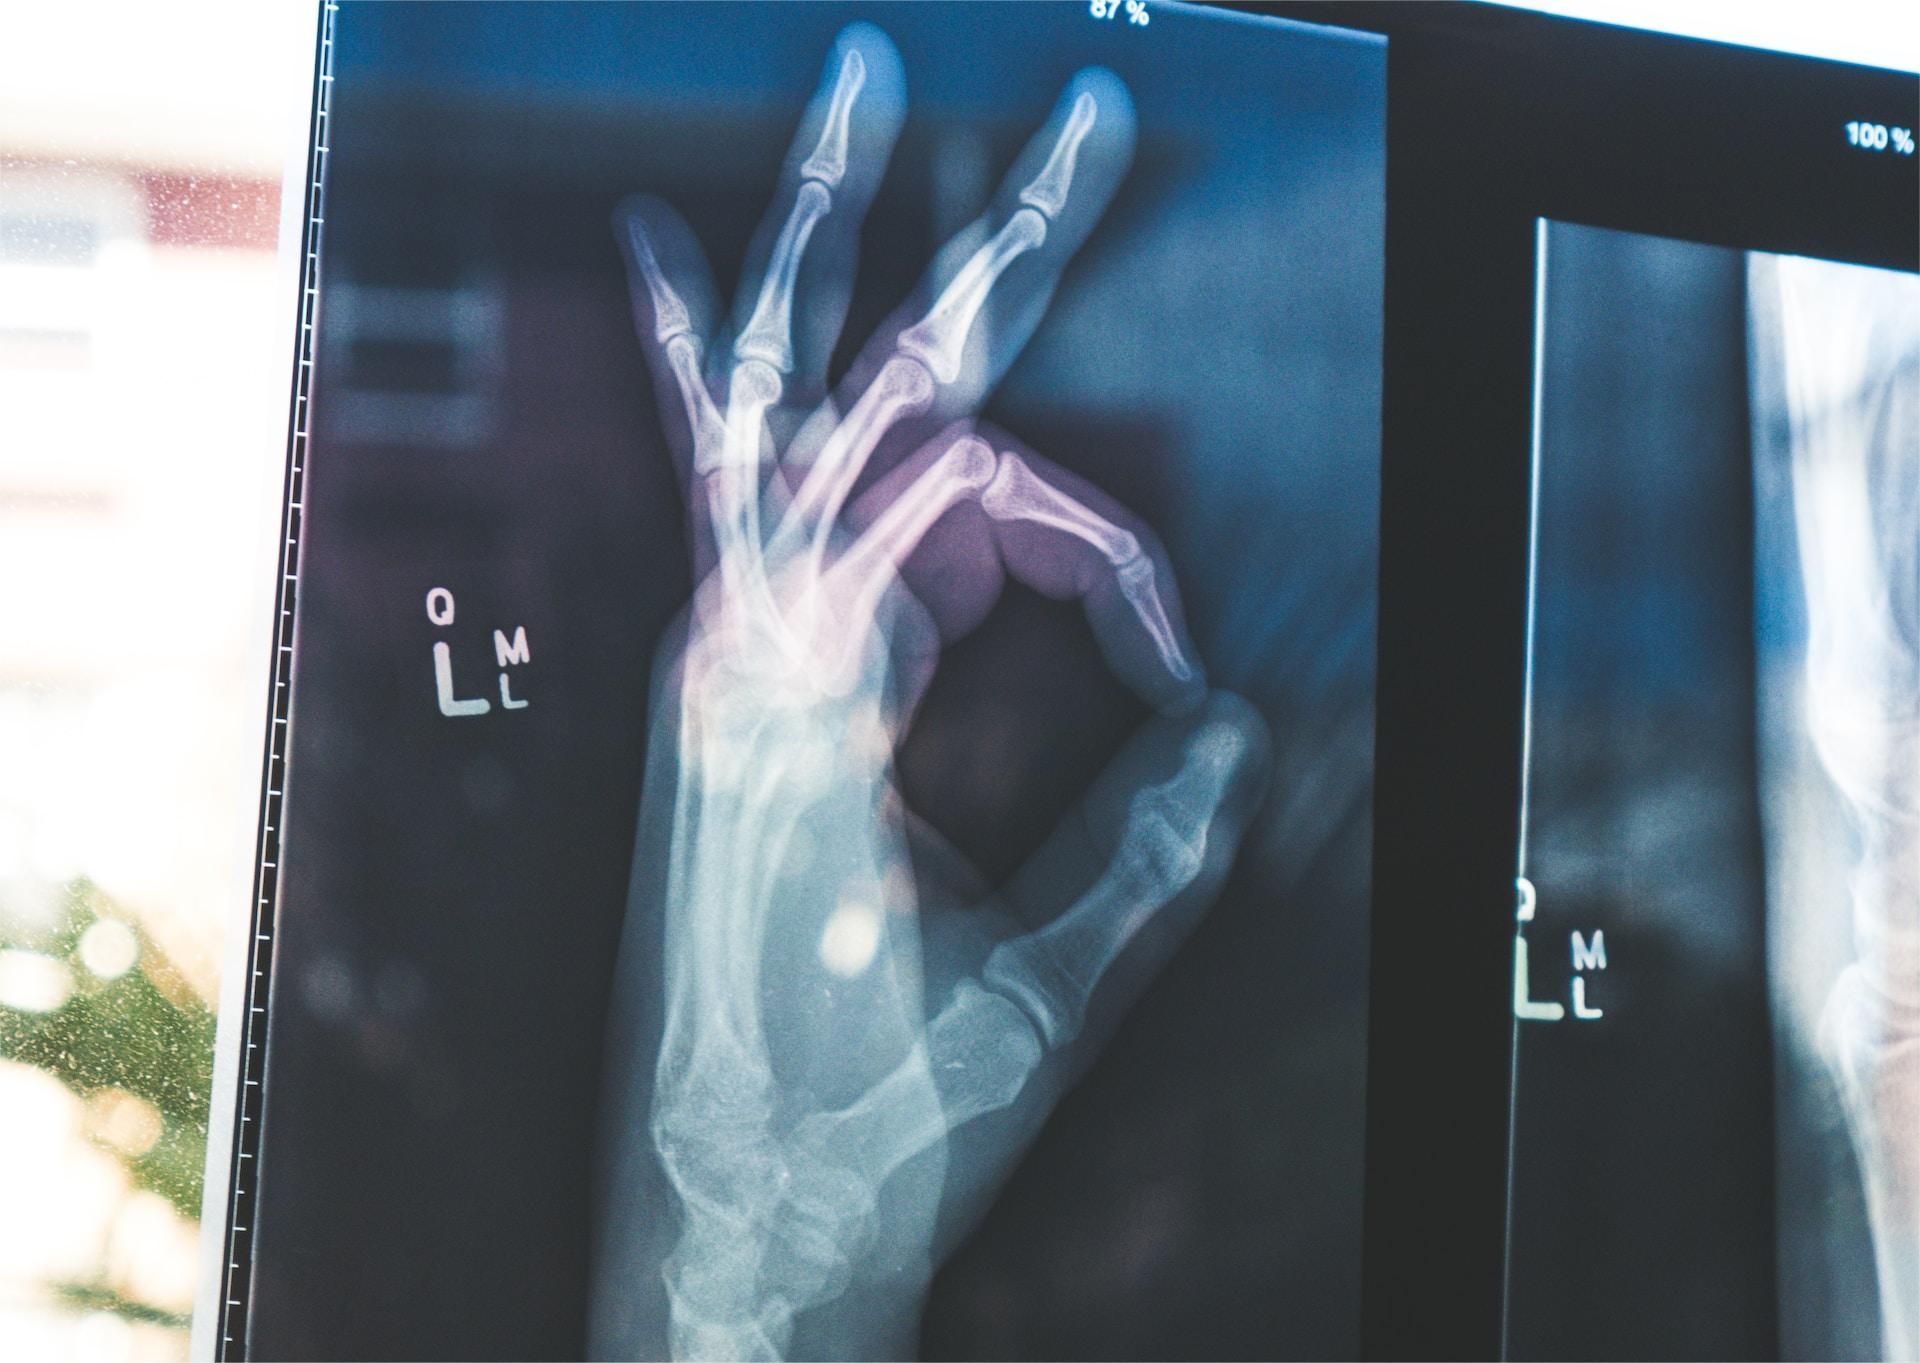

手是骨关节炎和类风湿性关节炎的常见部位,但这些疾病往往针对手部的不同关节。例如,在手上,类风湿性关节炎倾向于影响指关节,而骨性关节炎倾向于影响末端关节。

骨关节炎通常是根据体检和X射线诊断的。没有与骨关节炎相关的特异性血液检查异常。